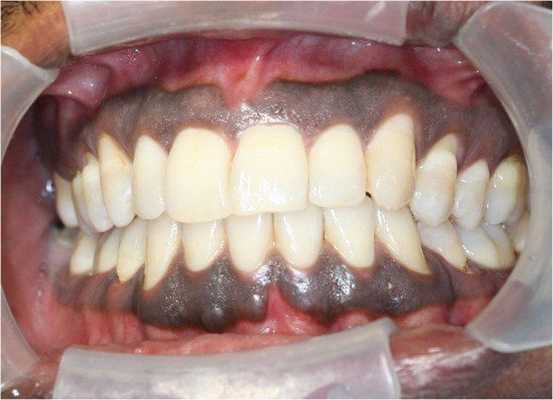

Мужчина, 42 года, обратился к врачу с жалобами на тёмные участки дёсен в области фронтальной группы зубов нижней челюсти. Пигментация наблюдалась с вестибулярной и язычной сторон в области резцов и клыка, а также в области 46 зуба (см. фото). Повышенная пигментация не была связана с какими-либо другими симптомами, пациент жаловался лишь на эстетический дефект. Два года назад заметил два небольших участка гиперпигментации, с тех пор участки увеличились в размерах. Пациент отрицал курение, употребление жевательного табака и алкоголя, семейный анамнез по данному заболеванию отсутствовал. При пальпации образование не было твёрдым, лимфоузлы не пальпировались. Анализ крови был в норме, на рентгенограмме не было никаких значительных изменений. Инцизионная биопсия помогла поставить диагноз «меланома полости рта». Пациент был направлен в ЧЛХ, терапия была начата немедленно, но в связи с высокой степенью злокачественности пациент скончался спустя 4 месяца после её начала.